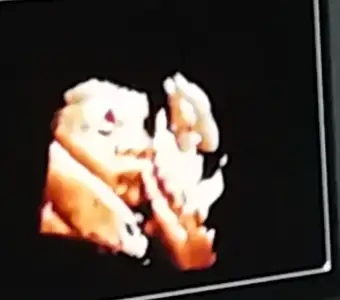

yaa bızım renklı pozlarımza bakın bugune dek bunları aldık 13haftalık biri dha 7cm ordaYok bize de renkli çıktı vermiyo canım. Sadece ekranda renkli görüyoruz ama doğru düzgün bi görüntü değil. O kadar paralar alıyolar bana da çok saçma geldi cihazlarının düzgün görüntü vermemesi. Bi de benim muayene 160 TL operator doktor. Seninki prof falan mı

yaa bızım renklı pozlarımza bakın bugune dek bunları aldık 13haftalık biri dha 7cm orda

Allah'ım ne tatlı özellikle en kucugu çok net çıkmış masallah kuzucuğa.yaa bızım renklı pozlarımza bakın bugune dek bunları aldık 13haftalık biri dha 7cm orda